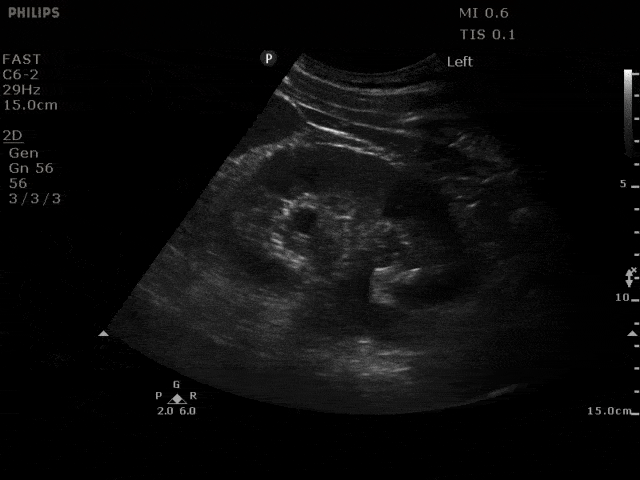

Mild - grade two hydronephrosis with dilation of the renal pelvis and dilation of the calyces. Grade one would not include dilated calyces.